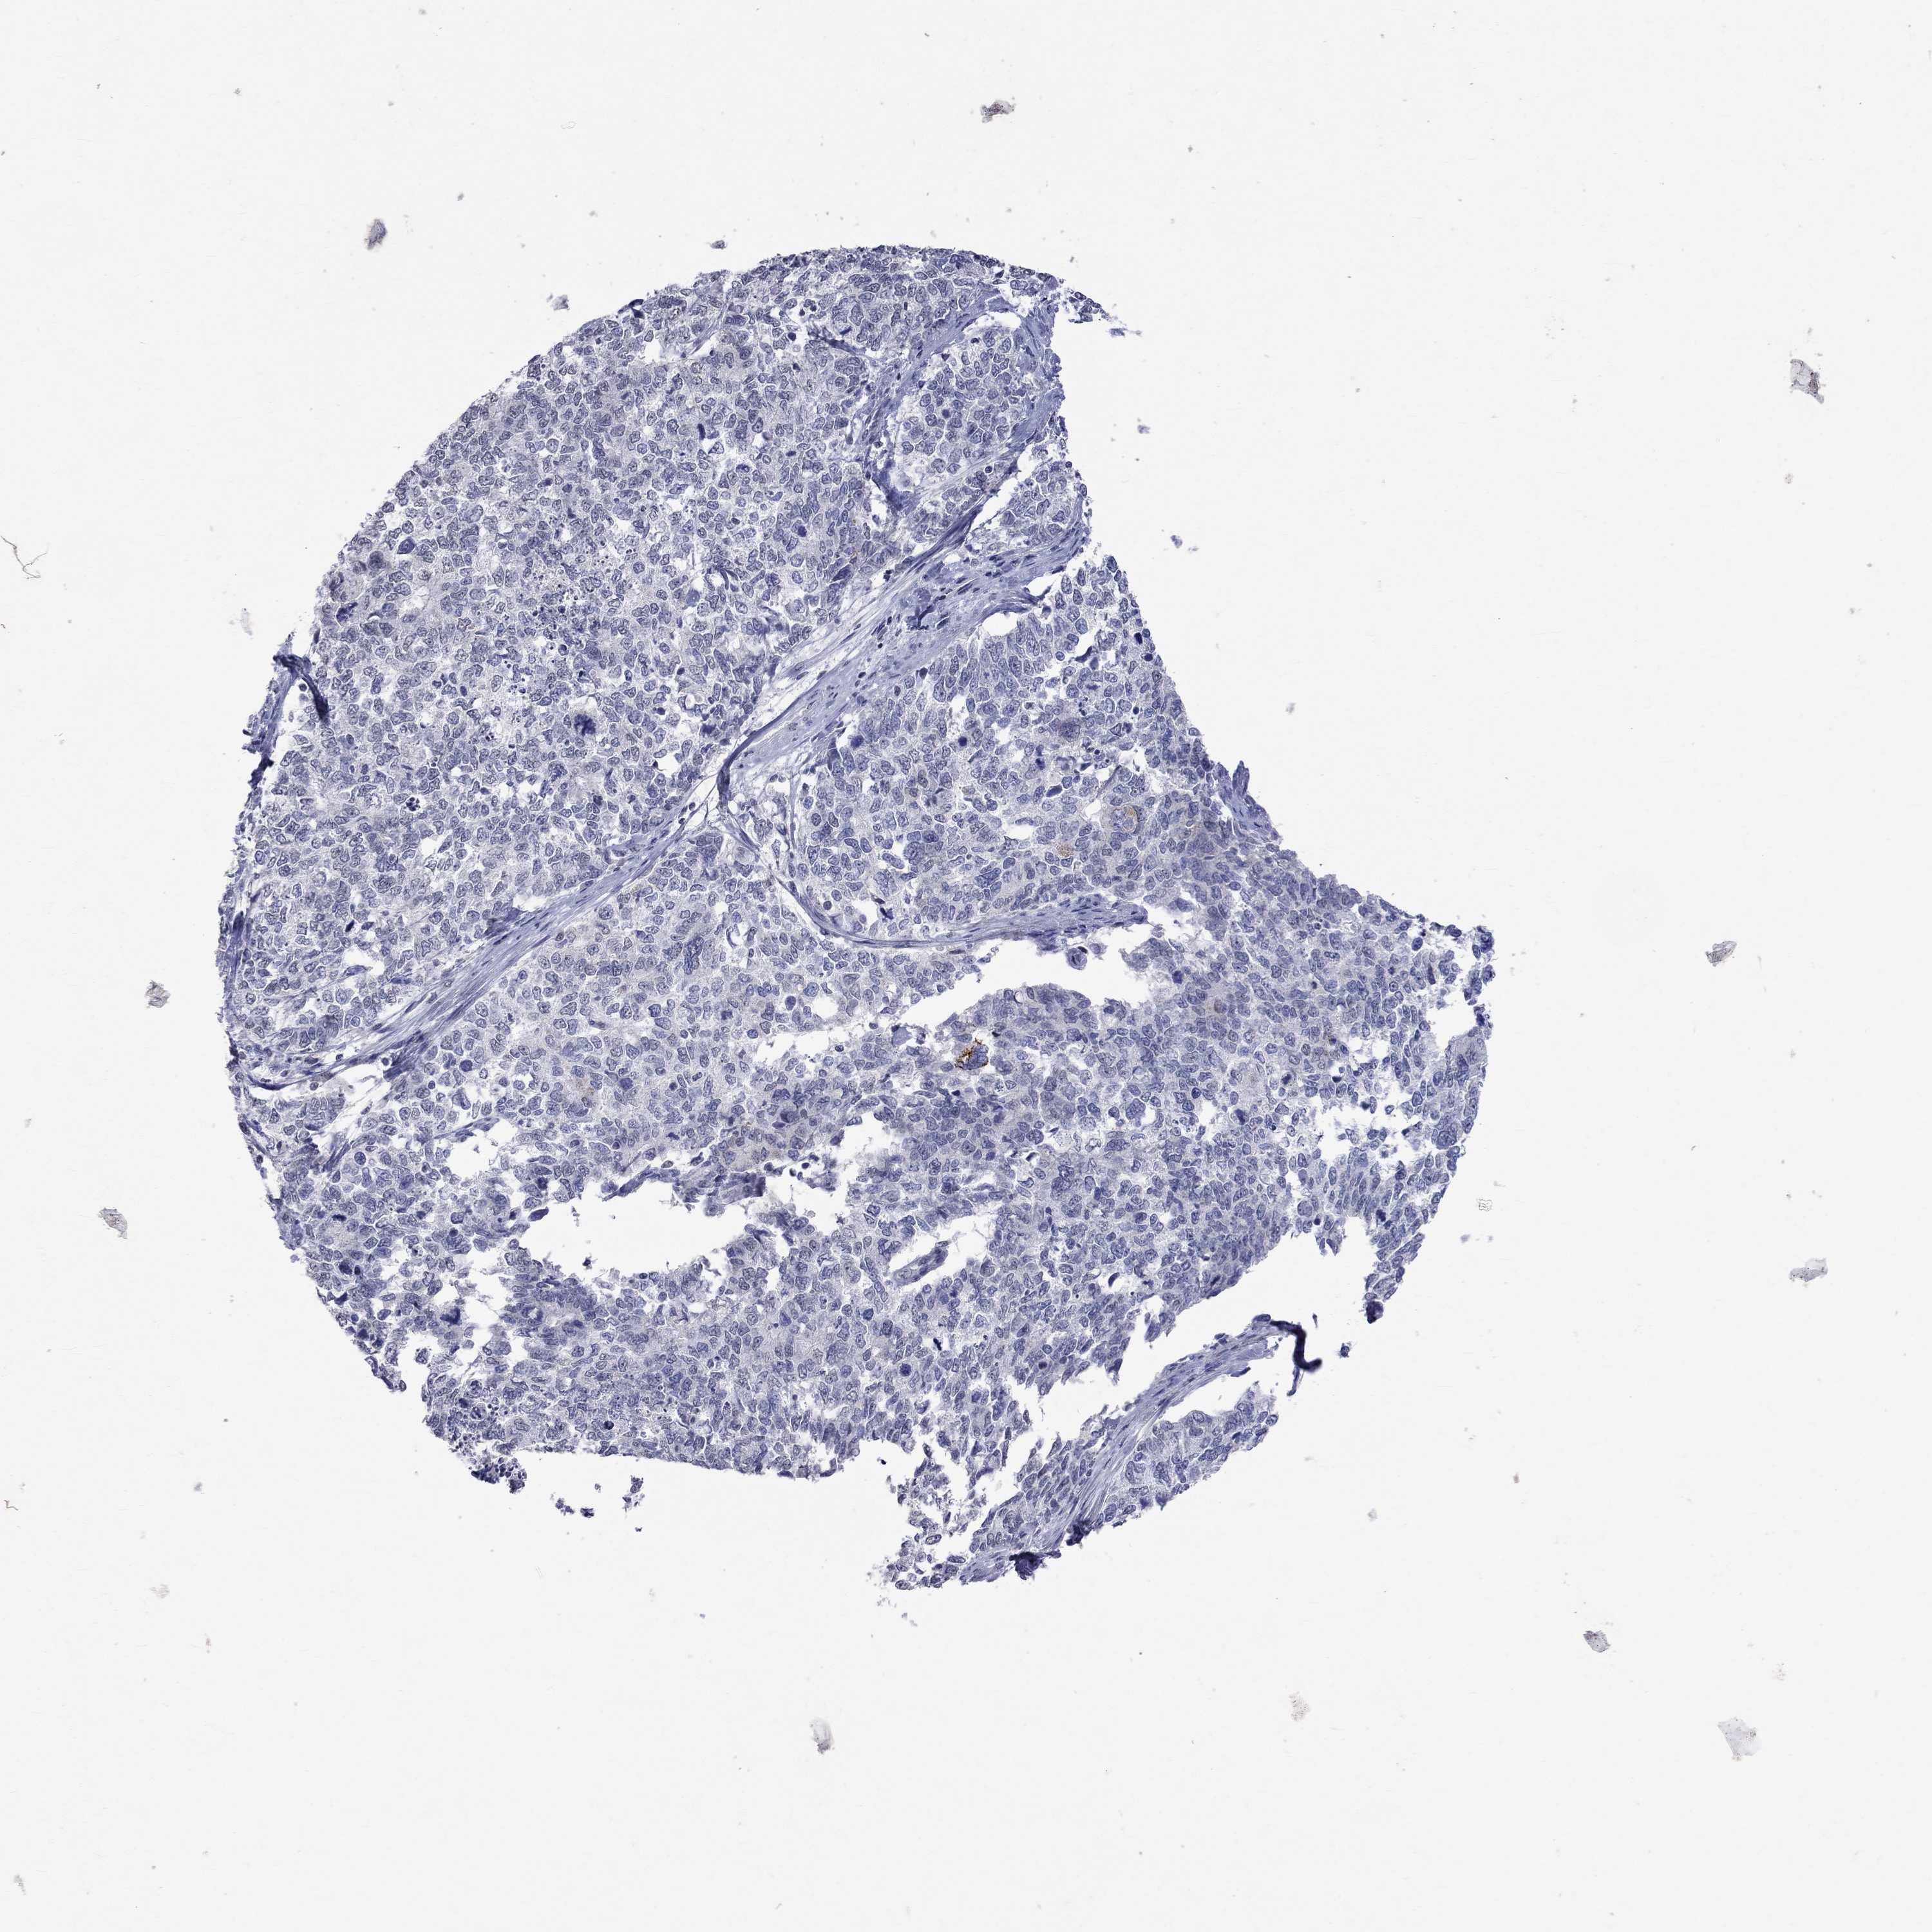

CERVICAL CANCER - Protein expressioni

A mouse-over function shows sample information and annotation data. Click on an image to view it in a full screen mode. Samples can be filtered based on level of antibody staining by selecting one or several of the following categories: high, medium, low and not detected. The assay and annotation is described here.

Note that samples used for immunohistochemistry by the Human Protein Atlas do not correspond to samples in the TCGA dataset.

Antibody stainingi

Antibody staining in the annotated cell types in the current human tissue is reported as not detected, low, medium, or high, based on conventional immunohistochemistry profiling in selected tissues. This score is based on the combination of the staining intensity and fraction of stained cells.

Each image is clickable and will lead to virtual microscopy that enables deeper exploration of all samples and also displays staining intensity scores, fraction scores and subcellular localization as well as patient and tissue information for each sample.

Antibody HPA014476

Antibody HPA058645

Staining

High

Medium

Low

Not detected

Intensity

Strong

Moderate

Weak

Negative

Quantity

>75%

75%-25%

<25%

None

Location

Nuclear

Cytoplasmic/membranous

Cytoplasmic/membranous,nuclear

Squamous cell carcinoma, NOS

Adenocarcinoma, NOS